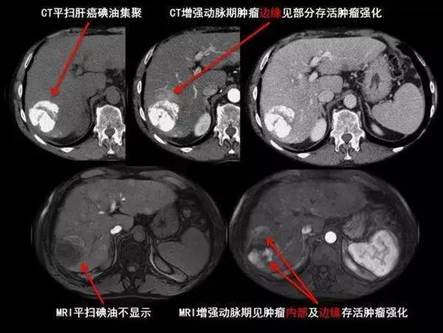

肝癌片子图,肝癌诊断书真实图片

肝癌ct片图片图解

肝癌ct图片